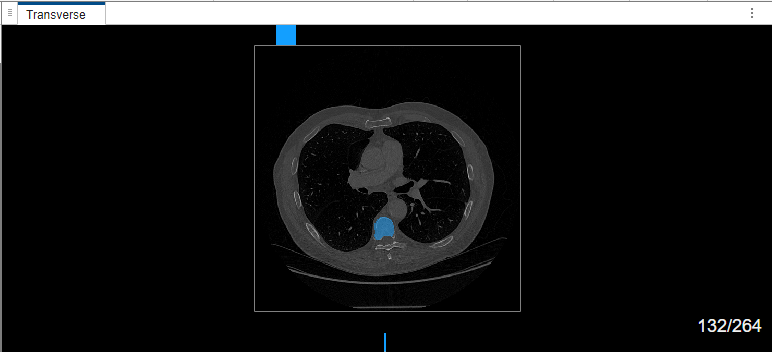

The MedSAM algorithm segments the object in the bounding box and labels it.